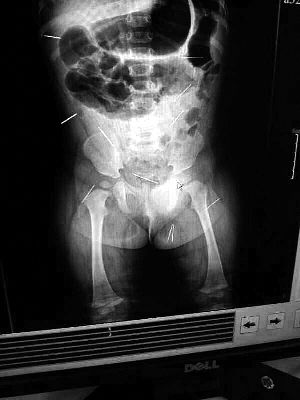

山東聊城11個(gè)月女嬰萱萱(化名)疑似被人以12根鋼針插滿臀部、腹腔等部位,昨天在兒童醫(yī)院會(huì)診后,醫(yī)生稱3根針靠近胸腔最危險(xiǎn),首批先行取出,預(yù)計(jì)將在下周二手術(shù)。孩子父母稱孩子一直由家人照顧,自家與他人并無(wú)冤怨。山東警方表示正在偵破中,不便透露案情。

“要不是當(dāng)初那幾個(gè)紅點(diǎn),可能到現(xiàn)在我們還不知道孩子身體里有鋼針!”昨天,在兒童醫(yī)院住院處,萱萱爸爸范先生稱,日前原本很愛笑的萱萱突然變得有些焦躁,一抱起來就哭,孩子母親偶然間在萱萱屁股上發(fā)現(xiàn)了幾個(gè)小紅點(diǎn)兒,原以為是蚊蟲叮咬,就醫(yī)結(jié)果卻讓人不寒而栗?!搬t(yī)院拍出的片子上,萱萱的體內(nèi)有12根鋼針,插滿臀部、腹腔、骨盆等各個(gè)部位?!狈断壬榻B,因?yàn)殇撫樢焉钊塍w內(nèi),要是孩子不哭鬧,他們很難發(fā)現(xiàn)。

北京晨報(bào)記者了解到,目前體內(nèi)的12根鋼針多分布在孩子的臀部,一根在腹部,其余3根在胸腔附近,其中一根很接近心臟?!耙?yàn)楹⒆犹。t(yī)生們害怕取針的時(shí)候?qū)λ斐蓚?,在胸腔附近?針可能會(huì)威脅她的生命”。

截至昨晚6時(shí)許,北京晨報(bào)記者從兒童醫(yī)院宣傳部門了解到,孩子目前已經(jīng)接受完專家會(huì)診,暫定今天和下周一進(jìn)行術(shù)前檢查,如果一切順利將在下周二手術(shù),“孩子暫時(shí)沒有生命危險(xiǎn)”。